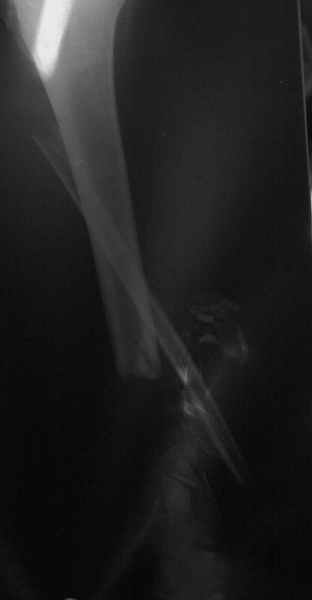

В приложении - моё наблюдение (возможно, уже представлял, тогда

извините).

Нога попала в пресс.

Ко мне больной попал черз 1,5-2 года после травмы и нескольких

операций с синегнойной инфекцией на всю голень. Меня пригласили на консультацию

насчет ампутации.

Лечил я его месяцев 8.

Малоберцовка полностью перестроилась, нога опороспособна.

При ходьбе на дальние расстояния пользуется тростью.

Осталась трофическая язва, периодически закрывается.

Клинические снимки где-то есть, но не очень качественные.

Один из вариантов.